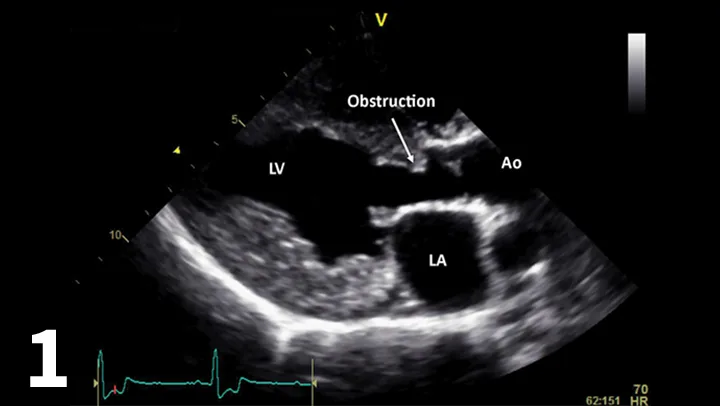

FIGURE 13A

Left-sided apical view optimized for the right ventricle and right atrium showing the high-speed diastolic flow from the right atrium into the right ventricle (A). Right-sided view of the right atrium and right ventricle. The tricuspid value does not open completely. However, after ballooning the diastolic inflow from the right atrium to right ventricle, it is more laminar and not as turbulent as it was before ballooning (B).